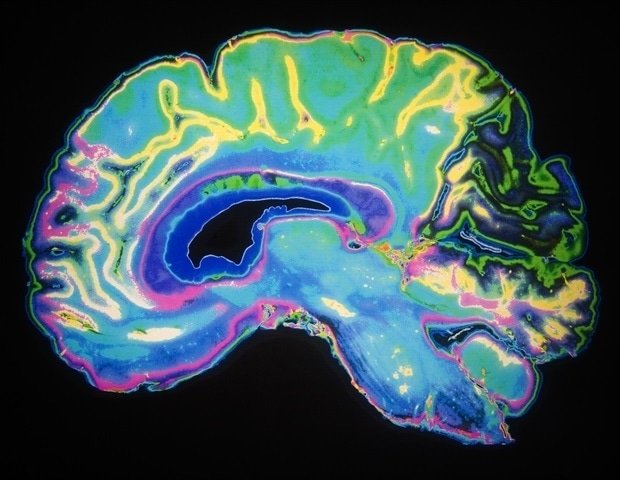

When a patient undergoes general anesthesia, the doctor has several drugs to choose from. Although each of these drugs acts on neurons in different ways, they all lead to the same result: a disruption of the brain’s balance between stability and excitability, according to a new study from MIT.

The researchers found that this disruption caused neural activity to become increasingly erratic, eventually causing the brain to lose consciousness. The discovery of this common mechanism may facilitate the development of new techniques for monitoring patients during anesthesia.

Exactly how anesthetic drugs render the brain unconscious has been a long-standing question in neuroscience. In 2024, research from Miller and Feete’s lab suggested that for propofol, the answer is that the anesthesia works by disrupting the balance between stability and excitability in the brain.

When a person is awake, the brain maintains this delicate balance, responding to sensory information and other input to return to a stable baseline.

“The nervous system has to work like a knife edge within this narrow excitability range,” Miller says. “You have to be excited enough so that the different parts influence each other, but if you get too excited you end up with a chaotic activity.”

In a 2024 study, researchers found that propofol takes the brain out of this state known as “dynamic stability.” As the drug dose increased, the brain took longer and longer to return to its baseline state after responding to new input. This effect became more and more pronounced until I lost consciousness.

This study showed that the same destabilization caused by propofol also appeared during administration of the other two drugs. This “universal feature” appears despite the fact that the three drugs have different molecular mechanisms. Propofol binds to GABA receptors and inhibits neurons that have those receptors. Dexmedetomidine blocks the release of norepinephrine. Ketamine then blocks NMDA receptors and suppresses neurons that have those receptors.

The researchers hypothesize that each of these pathways influences the brain’s balance of stability and excitability in different ways, each leading to a global destabilization of this balance.